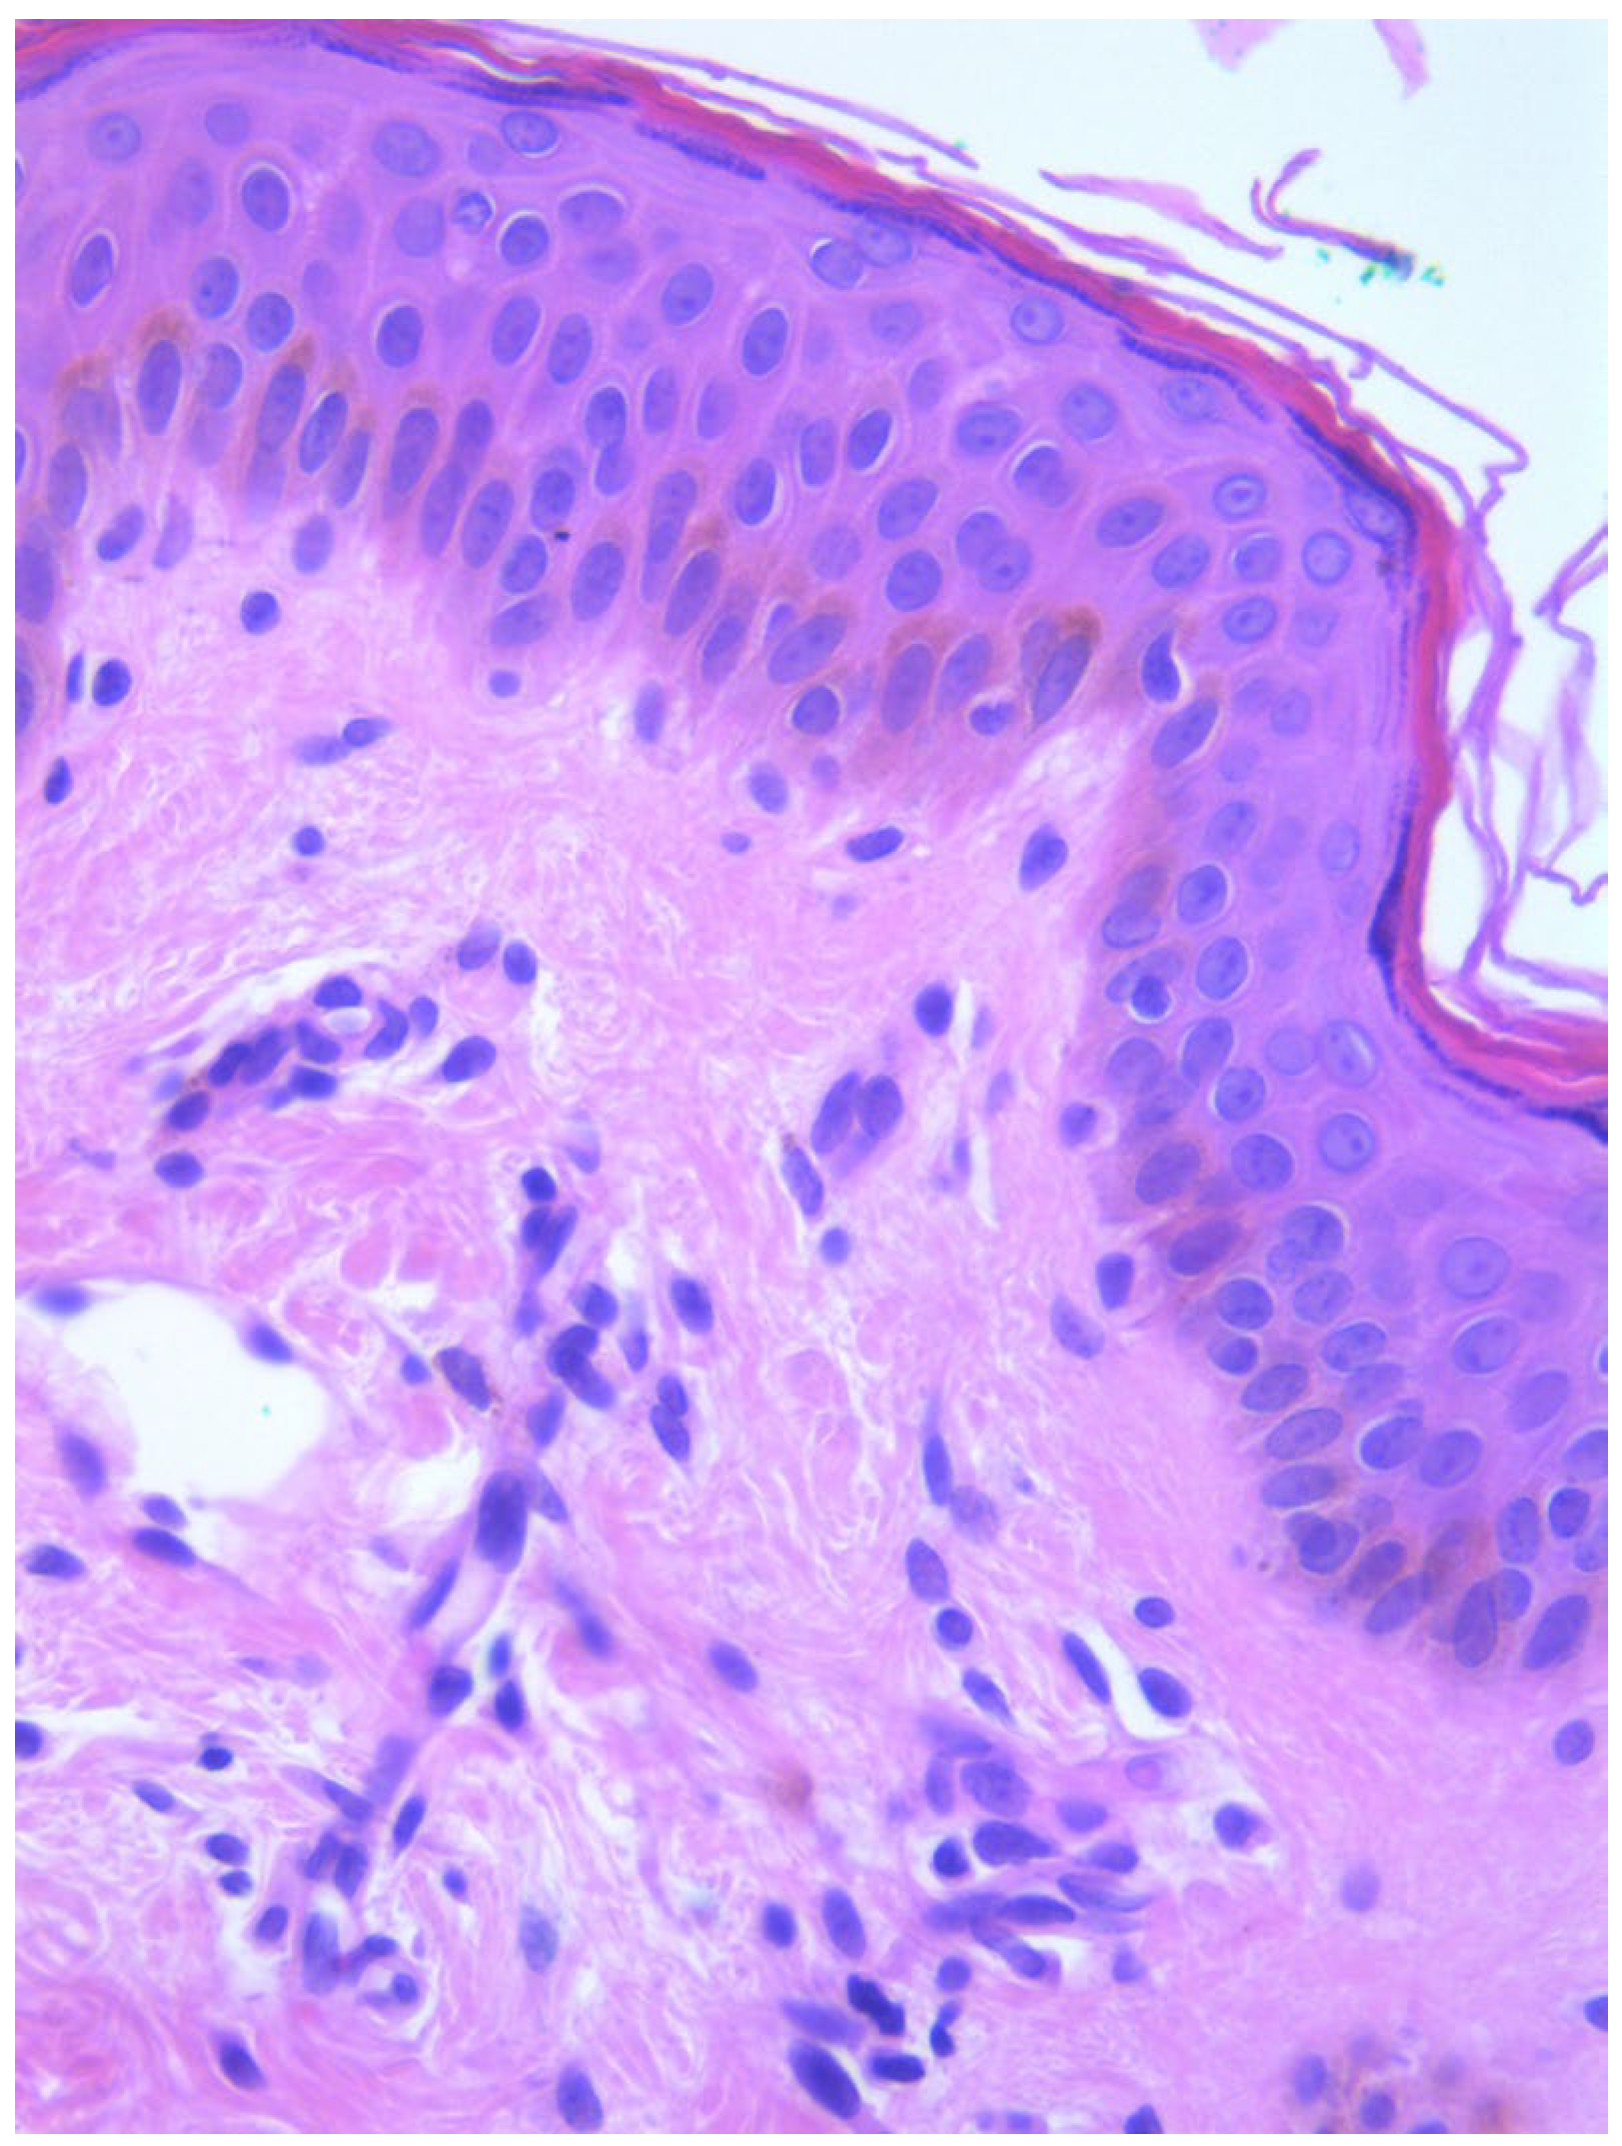

Two skin samples were taken from the upper and lower back, both showing slight, basal cell hyperpigmentation and an inflammatory infiltrate in the superficial dermis (Figure 3). Immunohistochemical stains with tryptase and CD117 showed that the infiltrate included mast cells (Figure 4), mostly with perivascular distribution. Mast cell count in six samples ranged from 11 to 12 mast cells per high-power view (CD117 and tryptase, respectively). The count per mm2 showed 34 mast cells with tryptase and 48 with CD117. C-kitD816V mutation analysis was not available. The bone scintigram did not detect any alterations and an abdominal ultrasound ruled out visceromegaly and only showed 10 mesenteric lymph nodes of non-specific appearance. He is currently under control and receiving oral levocetirizine 5 mg at night.

Figure 3. Slight basal cell hyperpigmentation and superficial inflammatory infiltrate (He, ×100).